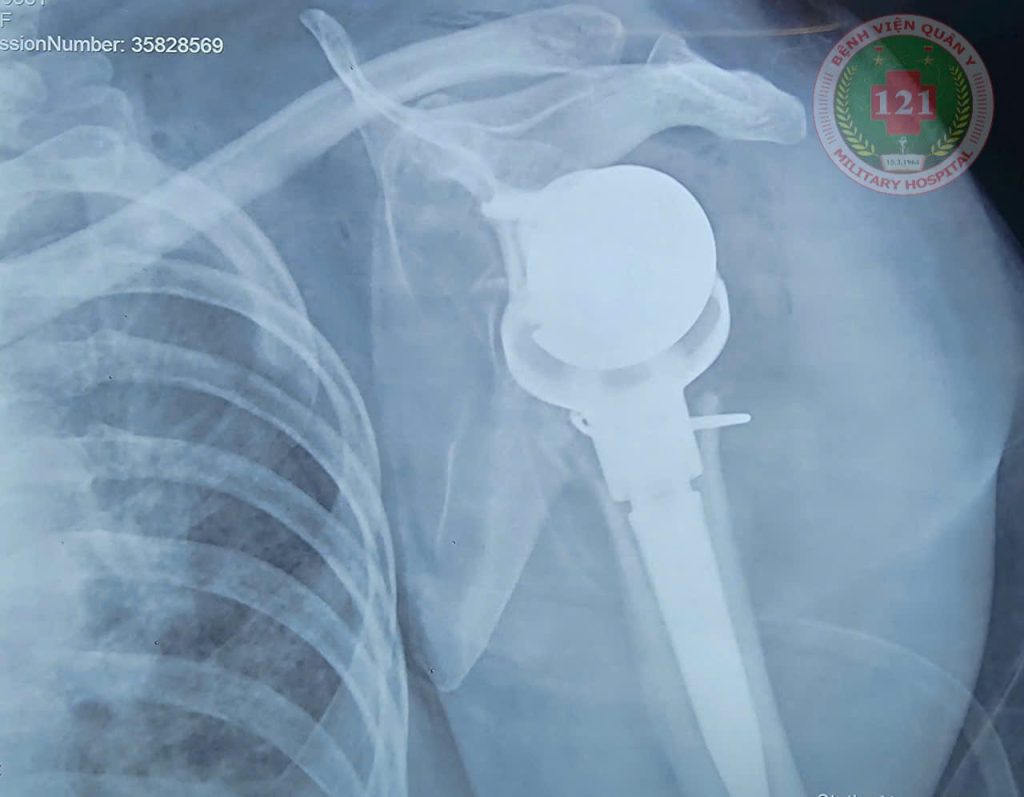

Ngay khi nhập viện bệnh nhân được chụp X-quang và chụp Cắt lớp vi tính dựng hình 3D xác định gãy trật phức tạp đầu trên xương cánh tay trái. Sau quá trình thăm khám và hội chẩn, các bác sĩ xác định cần tiến hành phẫu thuật thay khớp vai đảo ngược để phục hồi tốt nhất chức năng vận động cho bệnh nhân và phù hợp với xu thế hiện đại. Ca mổ đặt ra nhiều thách thức cho đội ngũ y bác sĩ bởi bệnh nhân có tiền sử đái tháo đường và thể trạng thừa cân, làm tăng nguy cơ biến chứng trong và sau phẫu thuật. Tuy nhiên, với tinh thần trách nhiệm cao cùng sự phối hợp nhịp nhàng của toàn bộ ekip, ca mổ kéo dài hơn 02 giờ đã diễn ra thuận lợi và thành công tốt đẹp.